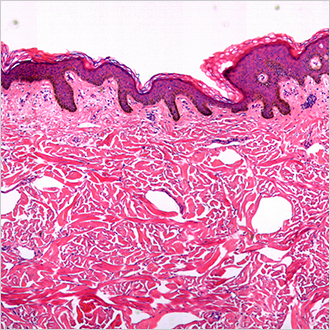

TM-Microscopy

This solution is used to optimise distribution and access to anatomo-pathology images by retrieving, storing, and supplying images via the TM-Microscopy viewer. It provides high-quality diagnostics thanks to improved relevance of the diagnosis of samples and better exchange between pathologists. Read more?